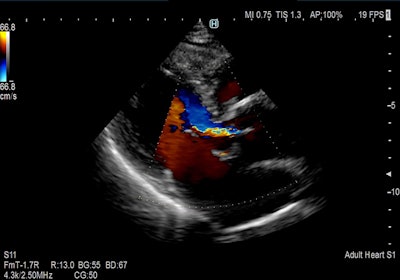

Hitachi is exhibiting three ultrasound scanners: Arietta 850 SE, Arietta 65, and Arietta 50. Arietta 850 SE is an upgraded version of Arietta 850 and features a 23-inch LCD monitor, shear-wave measurement and real-time tissue elastography for the assessment of liver stiffness, and Real-time Virtual Sonography, which offers image fusion for interventional procedures. Arietta 65 features Smooth Workflow and Superb Imaging tools and is useful for real-time elastography and auto intima-media thickness (IMT) measurement, while Arietta 50, the most compact model of the series, features a 21.5-inch monitor and can be used across various applications.

Color flow cardiac image acquired on Arietta 65 system. Image courtesy of Hitachi.